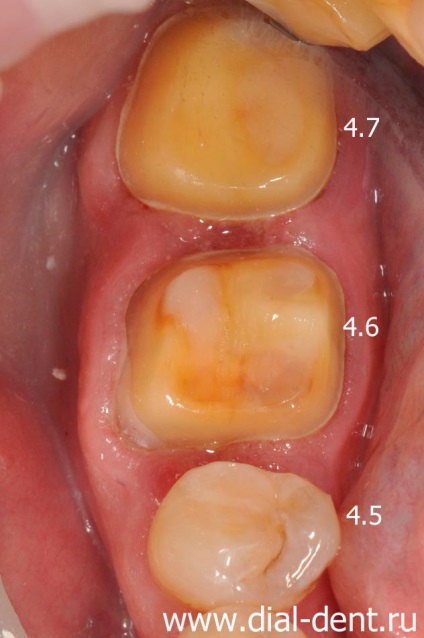

proteză

Patru dinți (1.6, 1.5, 4.6, 4.7) vor fi acoperite cu coroane ceramice, care le va consolida și de a restabili funcția de mestecat și aspectul.

Dinți pregătite pentru coroane, eliminate din impresiile dintilor.

La momentul de fabricare a coroanelor dentare dintii pacientului închis coroane temporare pentru a proteja dintii de sensibilitate de infecție și pentru a restabili aspectul.